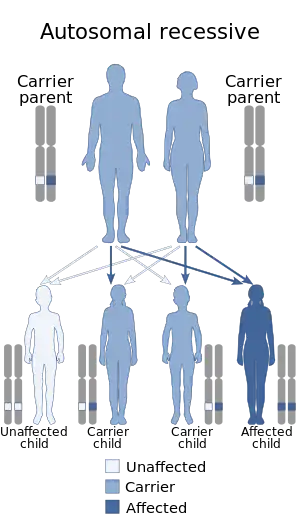

Nuclear DNA mutations

Nuclear DNA comprises most of the genome of an organism and in sexually reproducing organisms is inherited from both parents, in contrast to mitochondrial DNA's maternal pattern of inheritance. Leigh syndrome caused by nuclear DNA mutations is inherited in an autosomal recessive pattern. This means that two copies of the mutated gene are required to cause the disease, so two unaffected parents, each of whom carries one mutant allele, can have an affected child if that child inherits the mutant allele from both parents.[1]